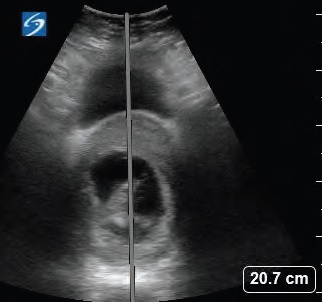

A 40-year-old female at 11 weeks, five days gestation presented to the emergency department (ED) with concern for lower abdominal pressure and inability to fully empty her bladder. She had urinary dribbling when standing and leaning forward. She denied fevers, back pain, saddle anesthesia, numbness, or weakness in the extremities. She reported no history of prior back surgeries, intravenous drug use, recent falls, trauma, or known inciting event. There was no vaginal bleeding or vaginal discharge. Transvaginal ultrasound (TVUS) performed in the outpatient setting a couple of weeks prior to presentation confirmed an intrauterine pregnancy (IUP) with a retroverted uterus. Straight catheterization resulted in approximately 1,500 mL of clear urine output and relief of symptoms. Urinalysis showed no evidence of infection, and the patient was discharged home.

Incarcerated gravid uterus is a rare diagnosis with an estimated incidence of one in 3,000 to one in 10,000 pregnancies.1-3 It most commonly occurs in patients with a retroverted uterus during weeks 10 through 16 of pregnancy. As the uterus grows, it can spontaneously correct; however, if the uterine fundus remains in the pelvis it can become trapped against the sacral promontory while the cervix is trapped against the pubic symphysis.1,4 Approximately 15 to 20 percent of all pregnancies occur in a retroverted uterine position, however only a rare minority of those pregnancies lead to IGU.1,5

Risk factors include prior abdominal surgeries, history of pelvic inflammatory disease, or prior history of uterine incarceration.6 IGU can be identified via history and physical, pelvic examination, or MRI. Alternatively, ultrasound can be utilized as a diagnostic modality. Transabdominal ultrasound is more helpful for IGU diagnosis than TVUS as the transabdominal approach allows for better visualization of the cervix in relation to the uterus.5,7 Since IGU is a rare presentation, the literature primarily consists of case reports and case series. Treatment options include Foley catheterization until the uterus spontaneously reduces and adopts a normal vertex presentation, having the mother adopt a knee-to-chest position, or manual reduction with appropriate pain control. More invasive techniques such as colonoscopic or laparoscopic reduction have been described.1,7